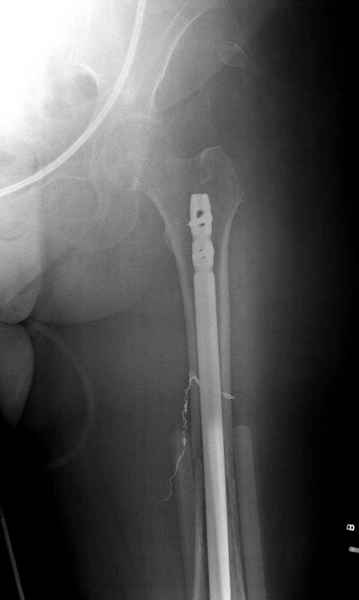

С минимальным рассверливанием и ретроградным методом провели остеосинтез бедра 12 мм гвоздем. (17-20)

Кровопотеря во время операции меньше 100 мл.

Больная выписана, взятый во время рассверливания материал изучается.